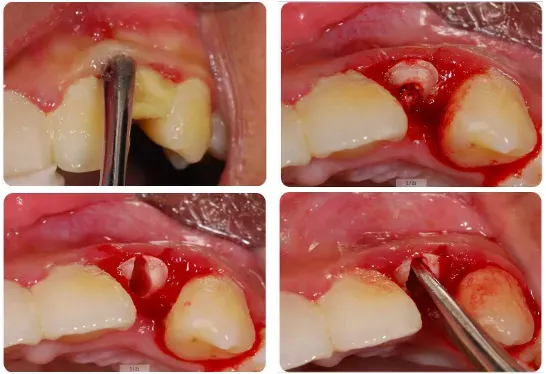

3、下颌第三磨牙的阻力分析及手术设计;

●下颌阻生第三磨牙的阻力分析及解除阻力要点

●什么样的角度分牙是合理并有效的

●通过图片和视频讲解各类下颌阻生第三磨牙的微创拔除方法

●通过病例分析手术中遇到问题解决思路